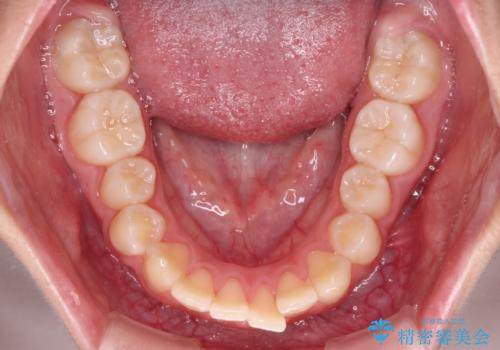

- 口元の突出感で口が閉じにくいとのことで来院された患者様です。

上下左右の第一小臼歯4本を抜歯し、ワイヤー装置での抜歯矯正を行うこととしました。